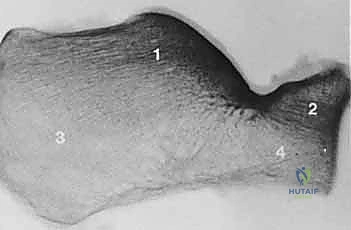

- الأشعة المقطعية (CT Scan): وهي الخطوة الأهم والأكثر حيوية. توفر الأشعة المقطعية صوراً ثلاثية الأبعاد وتقاطعاً دقيقاً للكسر، مما يسمح بتصنيف الكسر (نظام ساندرز - Sanders Classification) وتحديد عدد الشظايا العظمية ومدى انزياحها داخل المفصل. بناءً على هذه الأشعة، يضع الدكتور هطيف خطته الجراحية الدقيقة.

يُعد "النهج الجانبي الموسع" تقنية جراحية معقدة تتطلب مهارة استثنائية وإلماماً تشريحياً دقيقاً، وهو ما يتقنه الأستاذ الدكتور محمد هطيف ببراعة. يتيح هذا النهج رؤية شاملة وكاملة للجدار الجانبي لعظم الكعب والمفصل تحت الكاحل، مما يسمح للجراح بإعادة تجميع الشظايا العظمية بدقة متناهية كما لو كان يجمع قطع "الأحجية" (Puzzle).

بمجرد كشف العظم، يتم تنظيف التجمع الدموي. يقوم الجراح بكشف السطح المفصلي المكسور. باستخدام أدوات دقيقة، يتم رفع الشظايا العظمية المنخسفة إلى مكانها التشريحي الأصلي. يتم استعادة ارتفاع وعرض العظم، والأهم من ذلك، استعادة السلاسة التامة لسطح المفصل.

توضح الصور التالية مدى تعقيد الجراحة والدقة التي يتطلبها تثبيت عظم الكعب، والتي يعكسها التميز الجراحي للأستاذ الدكتور محمد هطيف: